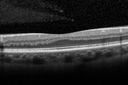

63 year old female with amblyopia more in the right eye than the left. SD OCT shows foveal aplasia VA 20/50 OD, 20/25 OS

fovealaplasia_demc_030615_01.jpg

Foveal hypoplasia - aplasia477 x angesehenSD OCT shows persistent plexiform layers in the center of the macula